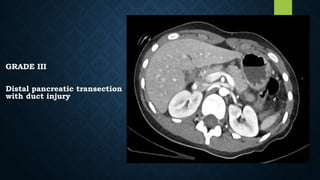

GRADE III

Distal pancreatic transection

with duct injury

GRADE III Distal pancreatictransection with duct injury